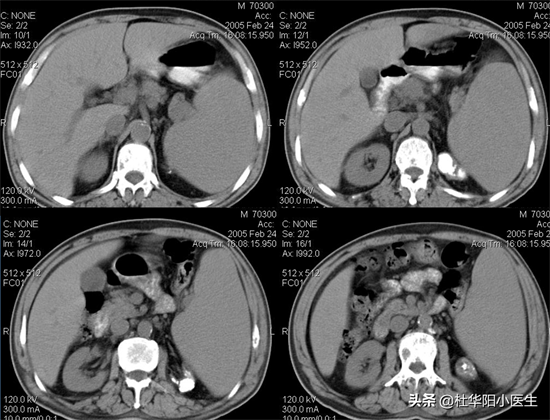

脾大

脾脏密度低于肝脏。增强后动脉期呈不均匀强化,门静脉期均匀强化。